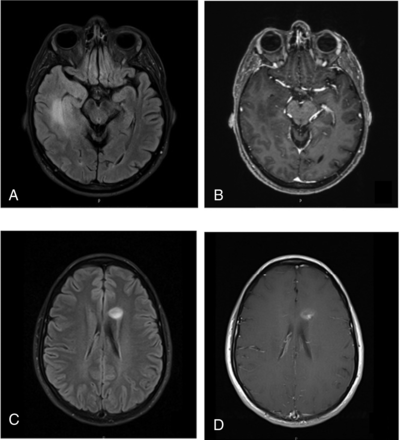

Representative cases of IDHwt LGGs. A 51-year-old man with an IDH wild-type diffuse astrocytoma. FLAIR (A) shows a 6-cm mass in the right temporal lobe with ill-defined margins. Contrast-enhanced T1WI (B) shows no contrast enhancement of the mass. This patient is deceased, with a survival time of 262 days. Further molecular testing in this case was positive for TERT promoter (−124 C > T) mutation. A 26-year-old woman with an IDH wild-type diffuse astrocytoma. FLAIR (C) and contrast-enhanced T1WI (D) show a 1.6-cm left frontal lobe mass with fairly well-circumscribed margins and contrast enhancement. This patient was alive at last follow-up, with a survival time of 2757 days. Further molecular testing in this case was positive for the BRAF V600E mutation.

Our finding that preoperative MR imaging has the greatest prognostic value for the IDHwt subtype is potentially explained by the increasingly well-recognized biologic and clinical heterogeneity of IDHwt LGGs, in particular based on molecular alterations such as telomerase reverse transcriptase (TERT) promoter mutation (Fig 2A, -B), epidermal growth factor receptor (EGFR) gene amplification, and chromosome 7/10 alterations.12,26,27,30 These molecular alterations have not yet been formally incorporated into the WHO classification scheme, and it is conceivable that some of our neuroimaging metrics correlated with these prognostically significant molecular alterations among our IDHwt cohort. We further speculate that our apparently counterintuitive finding of a positive correlation between contrast enhancement and survival time for the IDHwt cohort could be explained by the potential inclusion of B-raf proto-oncogene (BRAF)-mutant IDHwt gliomas in our cohort (Fig 2C, -D). BRAF-mutant diffuse gliomas commonly demonstrate contrast enhancement and are associated with favorable clinical outcomes.31⇓-33